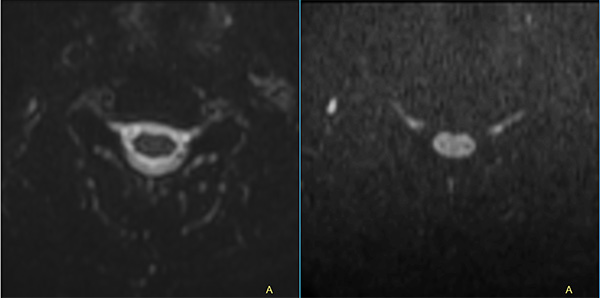

Comprehensive Cervical Spine imaging at 1.5T